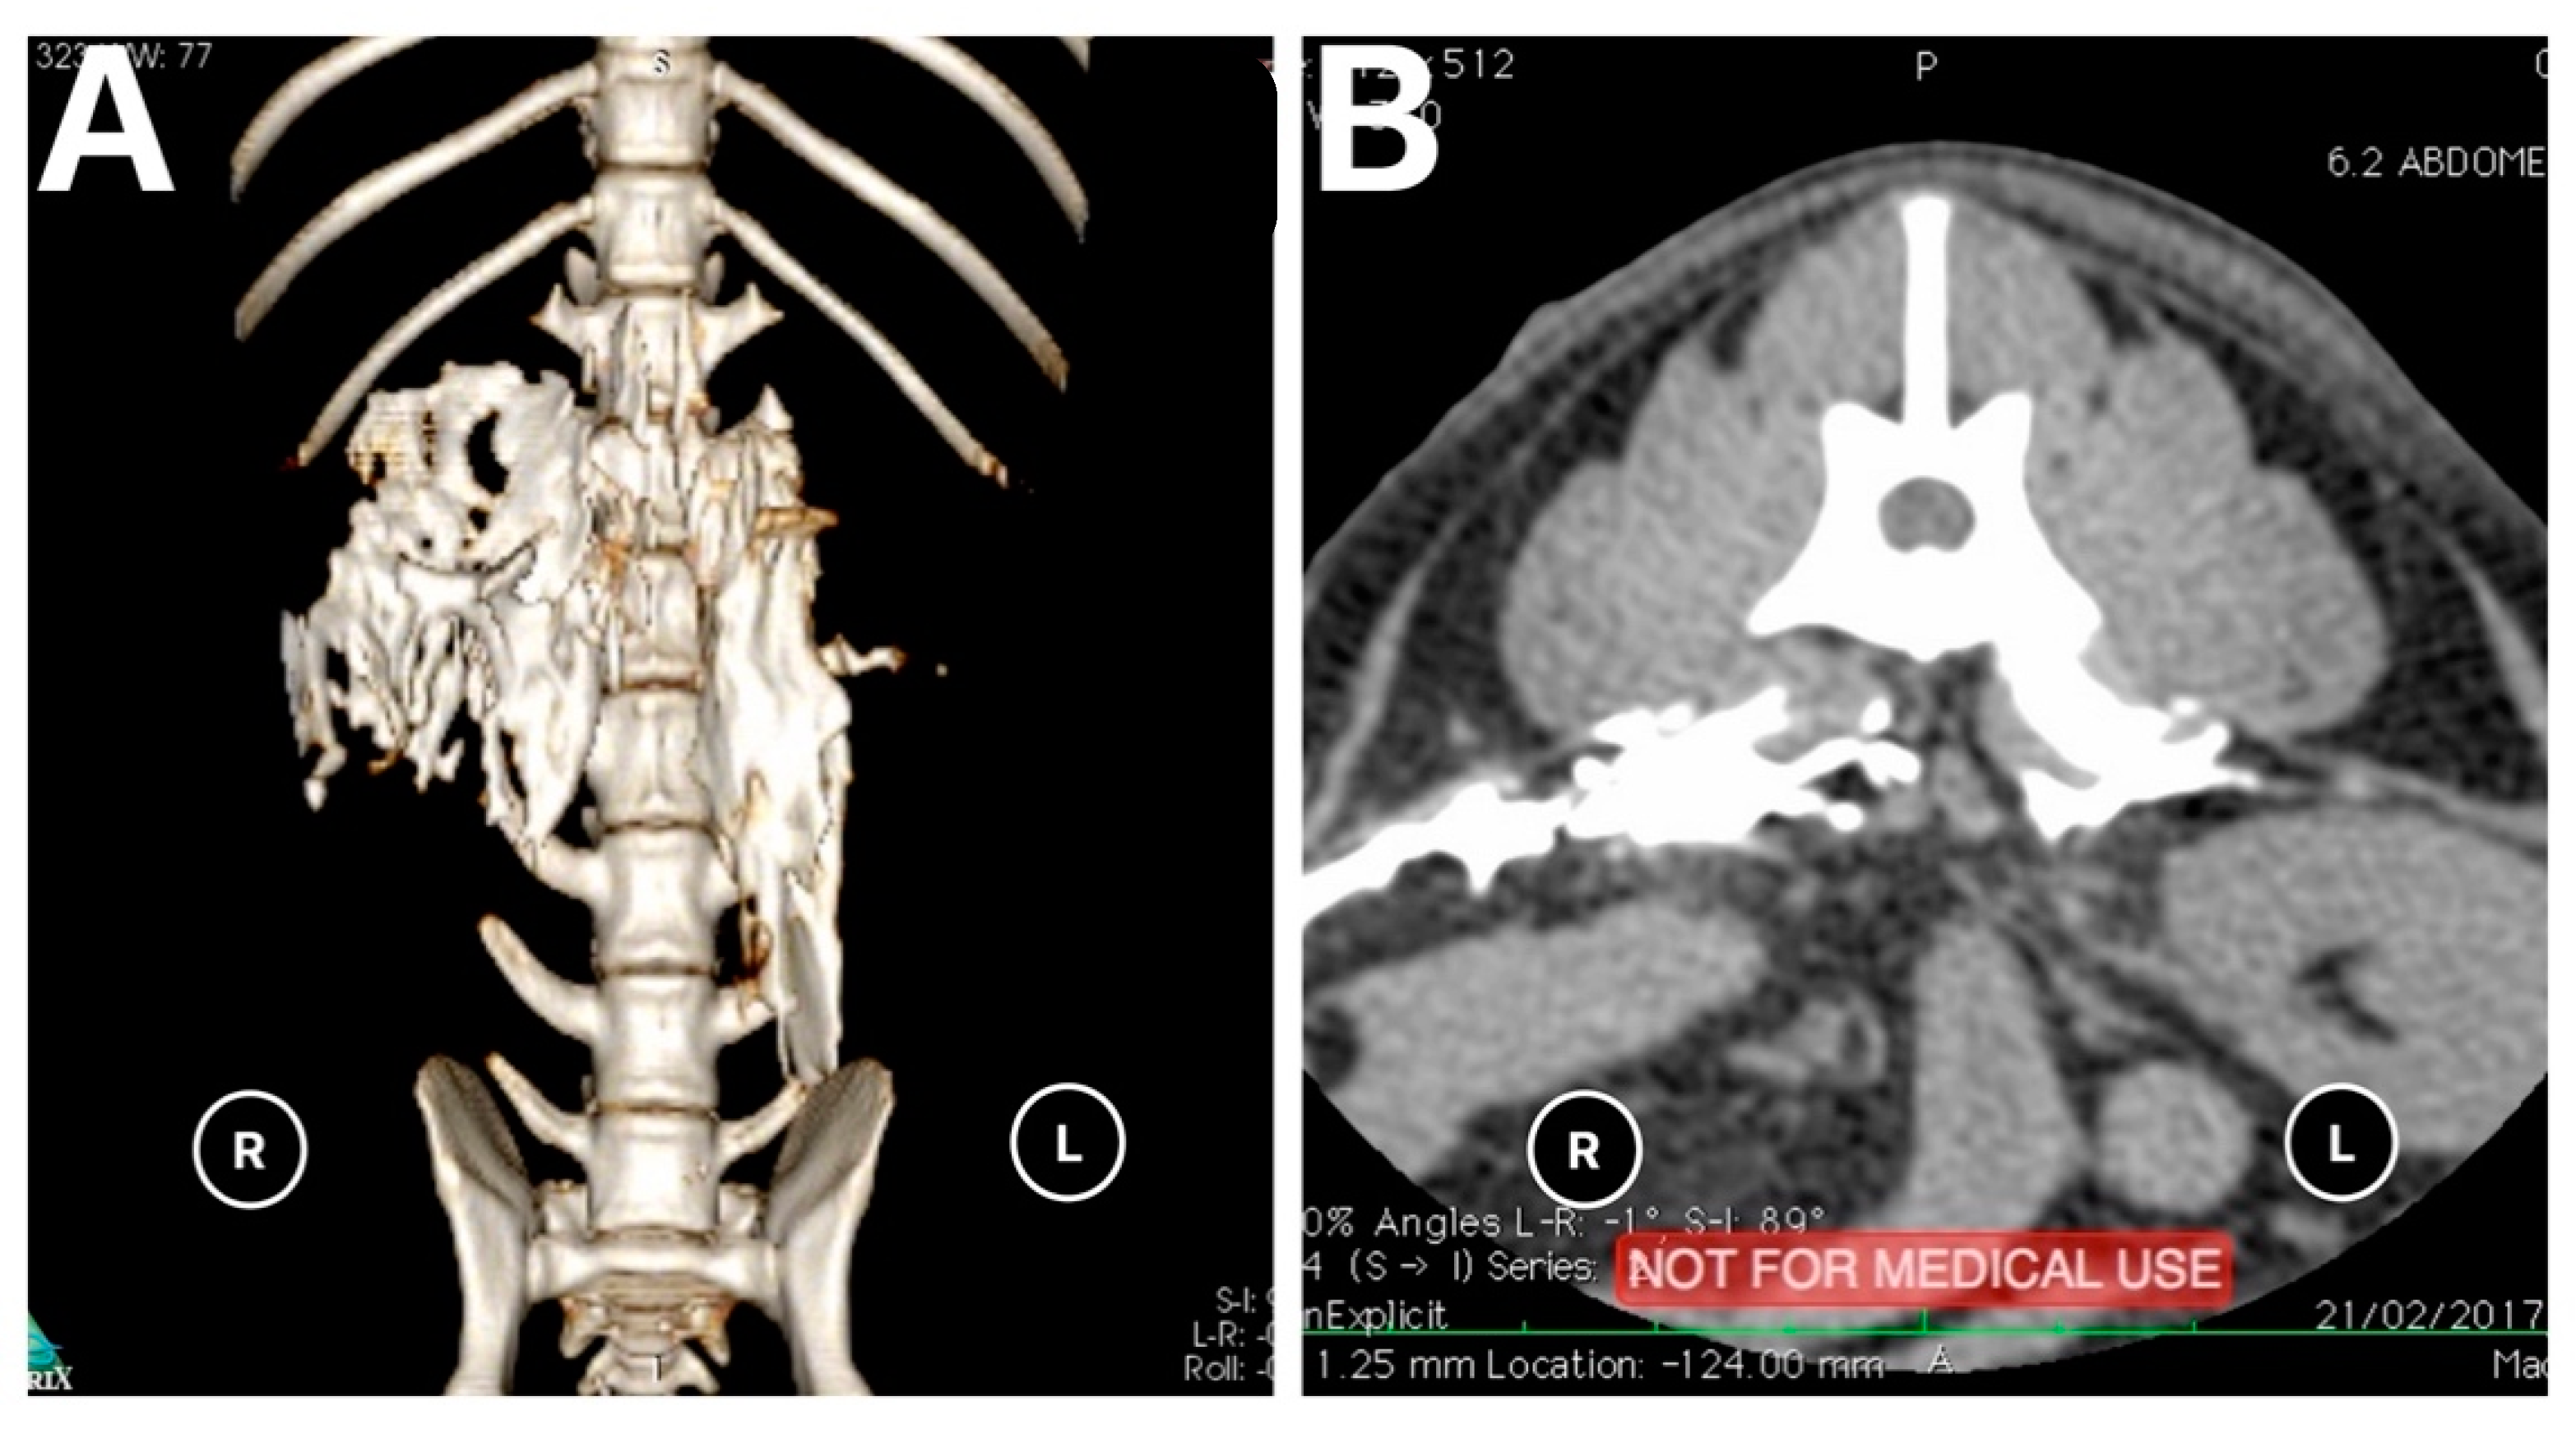

Figure 5. (A). 3D CT image of a carcasses showing a combined linear-lateral pattern of distribution of the mixture on the right and linear pattern on the left after performing the quadratus lumborum block. (B). Transverse view of CT image showing a lateral pattern on the right and linear pattern on the left.

The results of the distribution of the mixture in the CT images and dissection are summarised in Table 1 and Figure 4. On the basis of the CT images, we found that 4/18 (22.3%) injections showed a linear and lateralised pattern (Figure 5). Therefore, the mixture was visualised from the thoracolumbar fascia and moved towards the transversus abdominis plane. Conversely, 13/18 (72.3%) injections followed a linear pattern, and the mixture was always found between the quadratus lumborum and psoas muscle. No statistical differences were found between the distribution pattern or whatever side was used to spread the mixture, neither in CT images nor in dissection (p = 1).